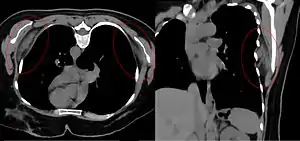

| Bilateral elastofibroma dorsi in native computed tomography: left image axial in prone position (for biopsy), right image oblique coronal view. |

By computed tomography, there is a poorly circumscribed, heterogeneous soft tissue mass, with a signal intensity similar to skeletal muscle. The fact that the lesion may be bilateral, helps eliminate a sarcoma from further consideration.[4] At US, elastofibromas are depicted deep to the musculature as a multilayered pattern of hypoechoic linear areas of fat deposition intermixed with echogenic fibroelastic tissue.[5] The mass often protrudes from the subscapular region upon shoulder abduction, allowing better delineation of the finding.[6]